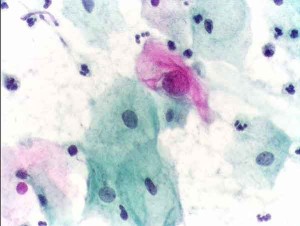

pap test abnormale